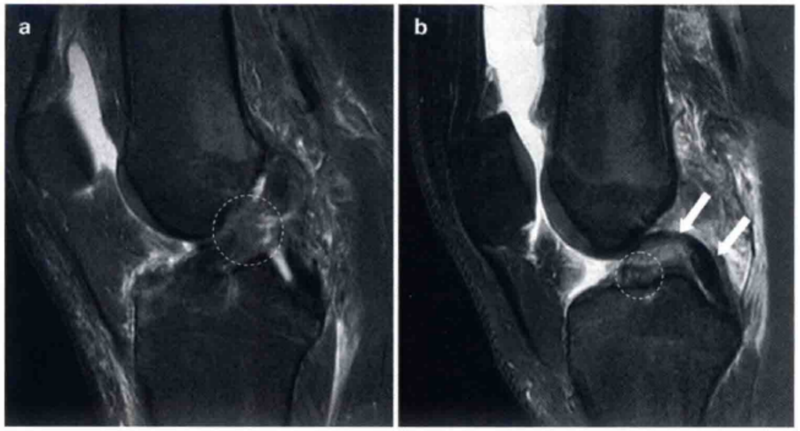

ACL损伤大部分发生于韧带的任何部位,但是最常见的为中间实质部的损伤。韧带信号不显影、不连续或者走行方向异常均提示ACL损伤。图2显示了典型的ACL损伤。与典型的ACL损伤相比,股骨止点处的损伤常常不易察觉(图3),尤其是在矢状位上或者开放低场强的MR1上更易忽略。此时,应该从水平位和冠状位片上去观察分析。尽管ACL结节样和黏液样退变没有明显的膝关节不稳,也无MRI特征性的表现,但是有时仍容易与ACL损伤相混淆(图4)。此外,对于任何类型的韧带慢性损伤,采用MRI诊断时均需慎重,已经瘢痕化但却无功能的ACL也可能在MRI上呈现完整的形态,甚至ACL断裂部位形成的瘢痕搭在PCL上而非股骨止点处(图5)。

图2 a和b显示的为2个不同患者ACL损伤的表现。

a显示韧带呈波浪形,并且实质部中部不连续(圆形标记)。在b中直接可以看到ACL胫骨侧的残端(圆形标记)。标记了正常的PCL(白色箭头)

图3 a和b显示的为冠状位质子加权像和轴位T2像,并在关节镜下证明了为ACL股骨端撕裂。

在a中ACL股骨止点的信号增强,并且不能看到切带附着点(圆形区)。在b中ACL股骨附着点缺失(圆形区)。将图3b与图1b对比观察可显示正常的股骨止点